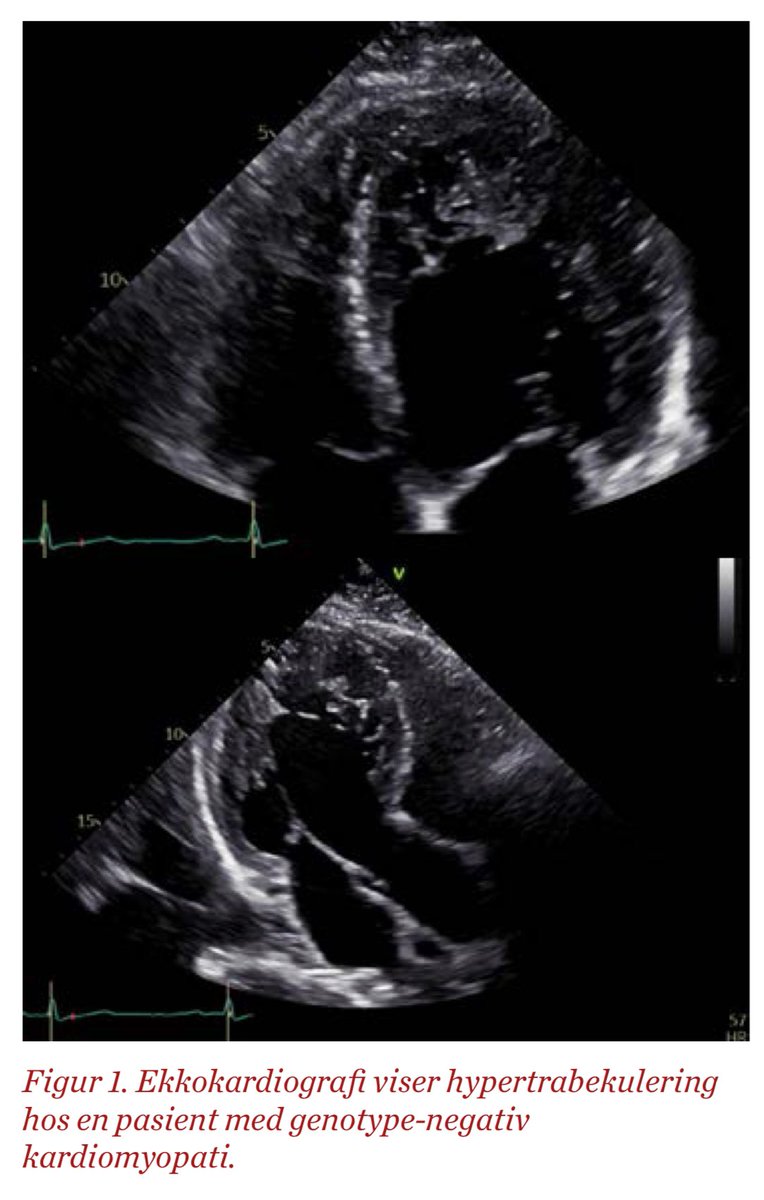

Non-compaction kardiomyopati. Hva er det og er det egentlig en egen entitet? Lær mer i denne grundige gjennomgangen av #NinaHasselberg @ProCardio1 https://t.co/gqjT4WguGF